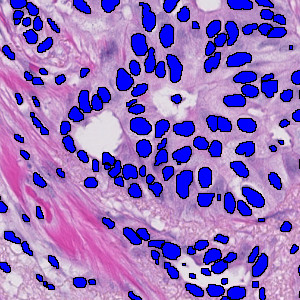

Figure 2

Nuclei segmentation in H&E stained tissue. The APP can be set to count the total number of nuclei.